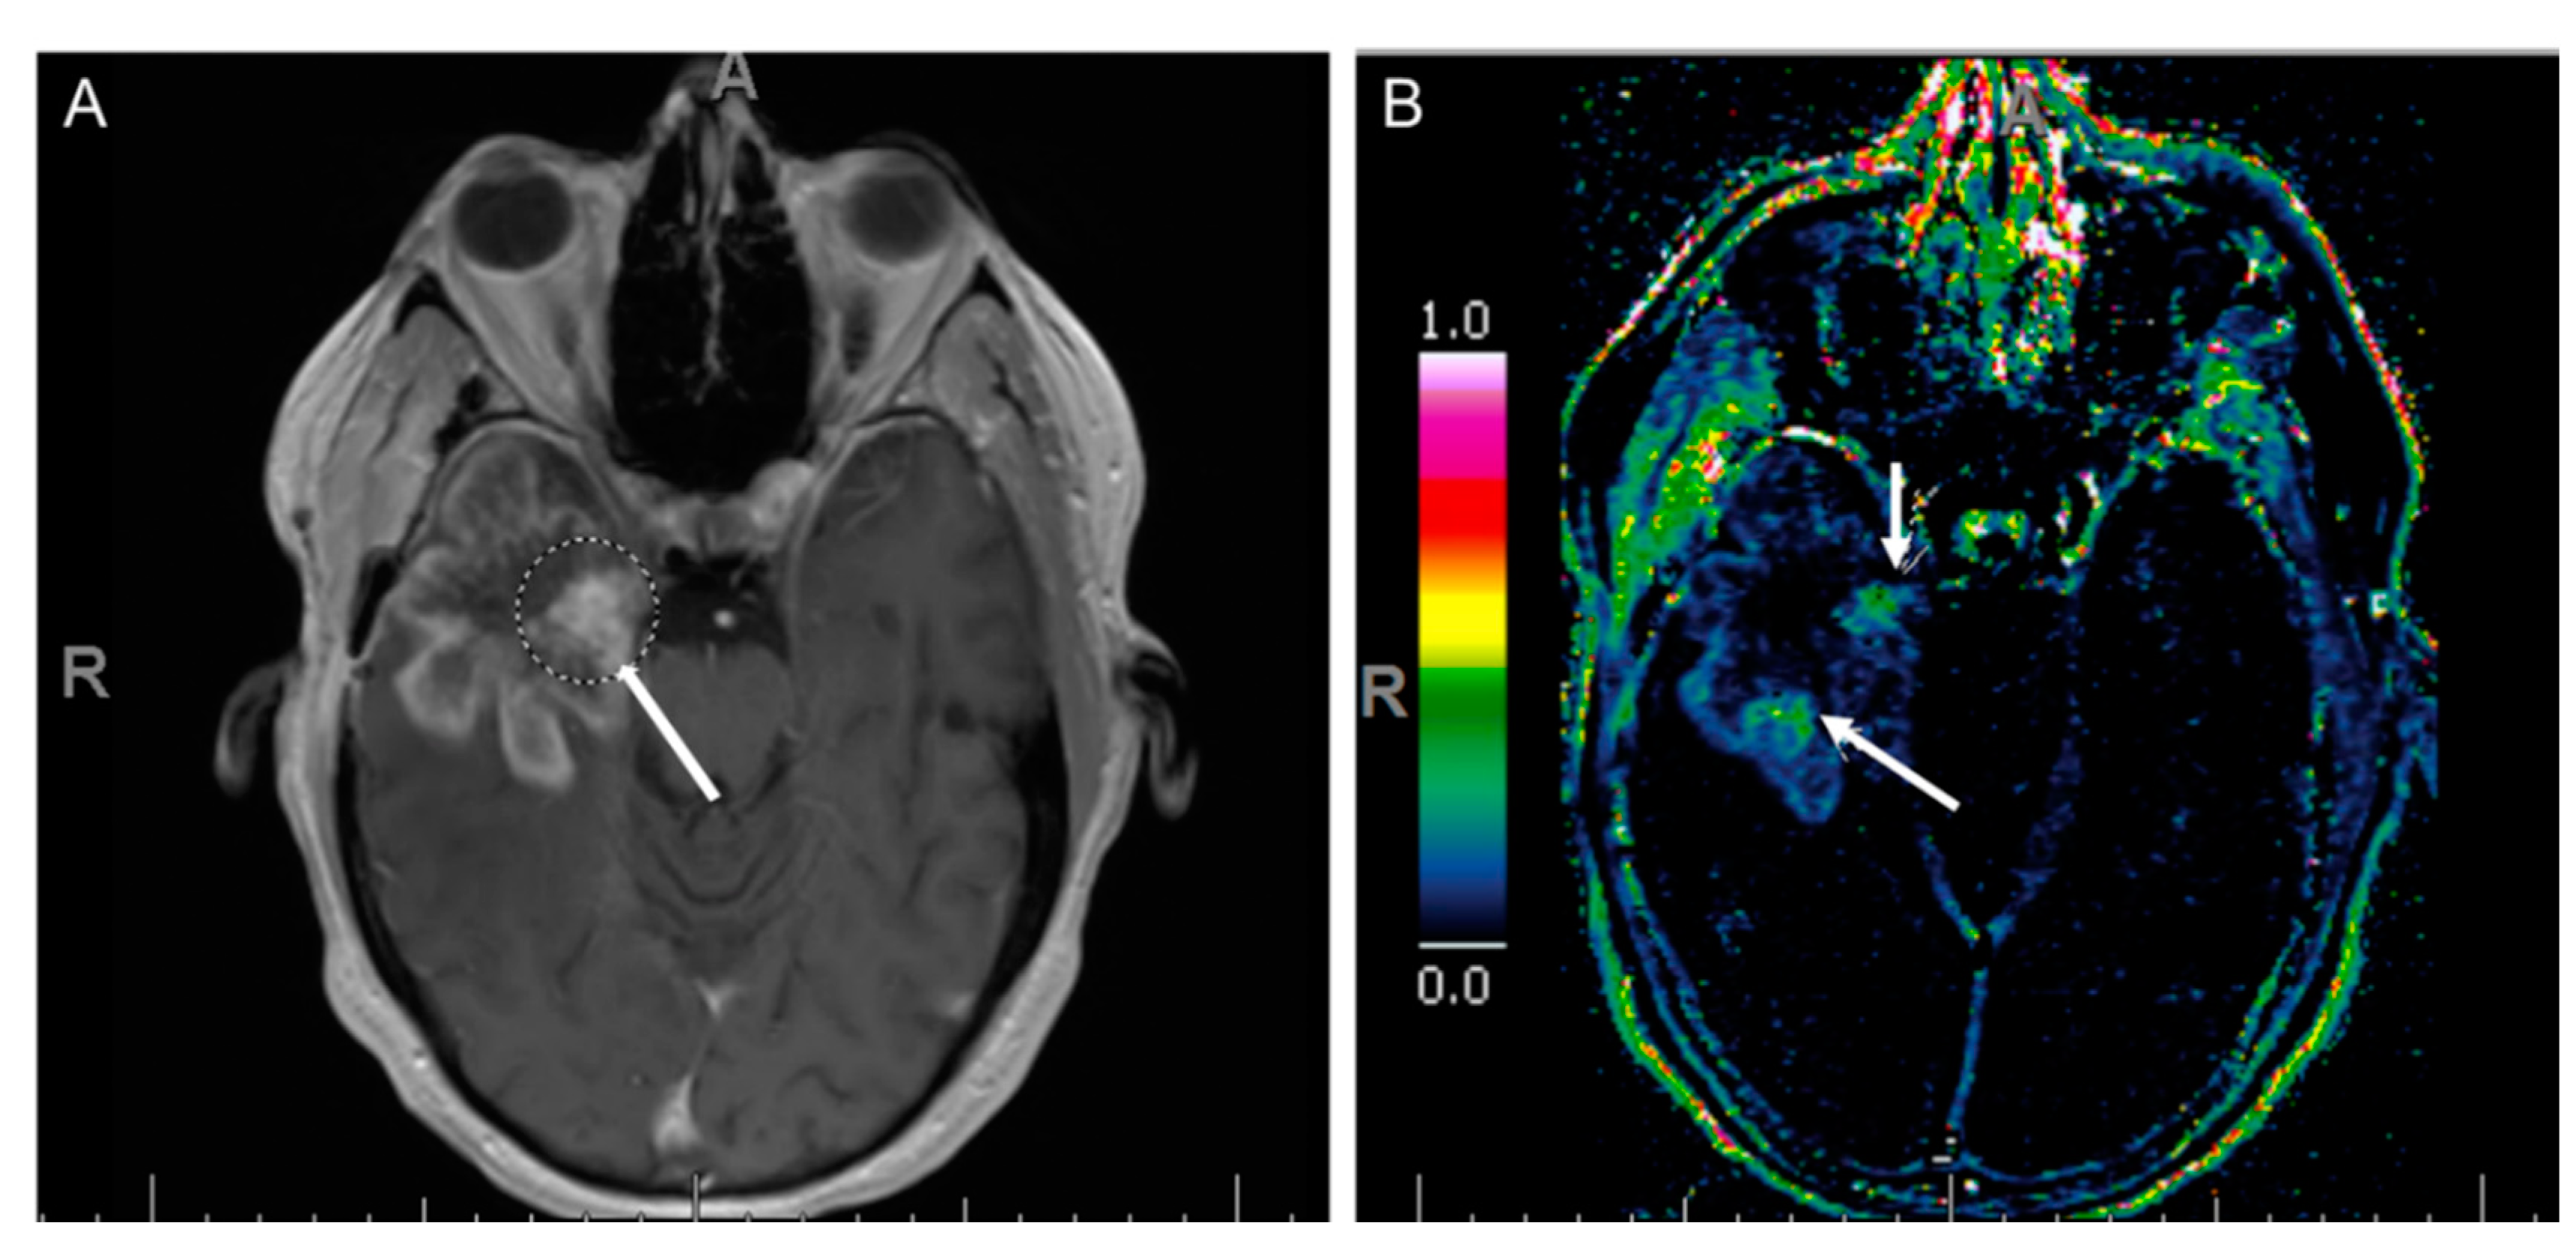

7.3. Dynamic Susceptibility Contrast (DSC) Perfusion MRI

- Jain, R.; Gutierrez, J.; Narang, J.; Scarpace, L.; Schultz, L.R.; Lemke, N.; Patel, S.C.; Mikkelsen, T.; Rock, J.P. In vivo correlation of tumor blood volume and permeability with histologic and molecular angiogenic markers in gliomas. Am. J. Neuroradiol. 2011, 32, 388–394. [Google Scholar] [CrossRef]

- Santarosa, C.; Castellano, A.; Conte, G.M.; Cadioli, M.; Iadanza, A.; Terreni, M.R.; Franzin, A.; Bello, L.; Caulo, M.; Falini, A.; et al. Dynamic contrast-enhanced and dynamic susceptibility contrast perfusion MR imaging for glioma grading: Preliminary comparison of vessel compartment and permeability parameters using hotspot and histogram analysis. Eur. J. Radiol. 2016, 85, 1147–1156. [Google Scholar] [CrossRef]

- Hilario, A.; Hernandez-Lain, A.; Sepulveda, J.M.; Lagares, A.; Perez-Nuñez, A.; Ramos, A. Perfusion MRI grading diffuse gliomas: Impact of permeability parameters on molecular biomarkers and survival. Neurocirugía 2019, 30, 11–18. [Google Scholar] [CrossRef]

- Provenzale, J.M.; Wang, G.R.; Brenner, T.; Petrella, J.R.; Sorensen, A.G. Comparison of permeability in high-grade and low-grade brain tumors using dynamic susceptibility contrast MR imaging. Am. J. Roentgenol. 2002, 178, 711–716. [Google Scholar] [CrossRef]

- Zhang, J.; Liu, H.; Tong, H.; Wang, S.; Yang, Y.; Liu, G.; Zhang, W. Clinical applications of contrast-enhanced perfusion MRI techniques in gliomas: Recent advances and current challenges. Contrast Media Mol. Imaging 2017, 2017, 7064120. [Google Scholar] [CrossRef] [PubMed]